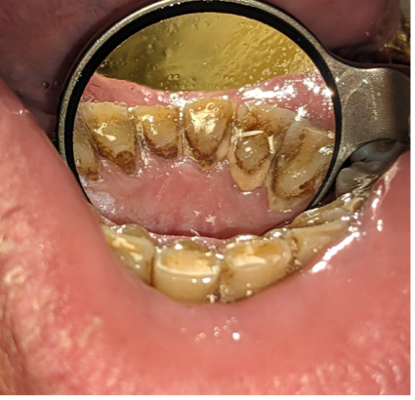

Beyond appearance, however, oral hygiene plays a crucial role in overall health. Poor oral health (Figures 1 and 2) has been linked to cardiovascular disease, diabetes, adverse pregnancy outcomes, neurodegenerative diseases (including Alzheimer’s disease), and several cancers. Oral cancer alone is the 6th most common cancer worldwide, and in the U.S. the average 5-year survival rate is only 64.3%, dropping to 38.5% when diagnosed after metastasis [2].

Figure 1. Plaque accumulation on the lingual anterior mandibular teeth